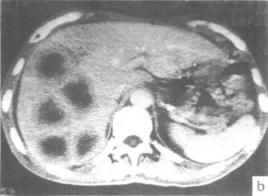

2)CT:是目前診斷肝轉移灶較為精確的方法,CT的優點是掃描切面固定,在病灶觀察中可以動態對比,較為客觀,敏感性高於超聲。CT的缺點是特異性較差,對於小結節、瀰漫性、微小癌灶等敏感性欠佳,可能漏診部分病例。